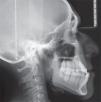

The cephalometric data showed a skeletal class III patient due to prognathism with a brachifacial pattern, a neutral growth tendency and upper and lower incisor proclination (Figure 3yTable I).